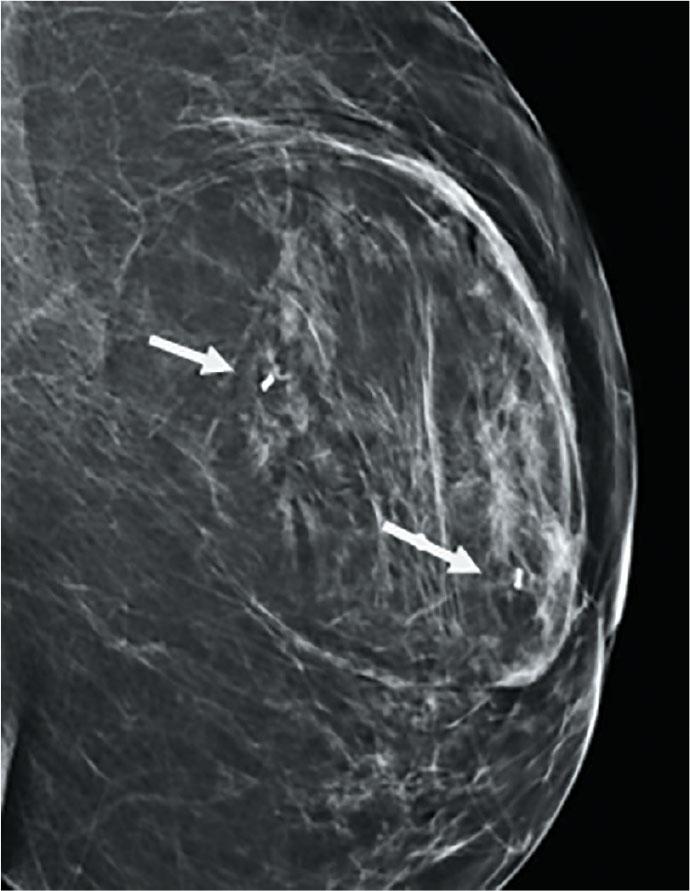

A 61 year old woman was recalled for assessment after a screening mammogram. She was known to have long standing benign lump in her left breast which had shown interval development of central distortion. On clinical palpation, there was mobile mass in left breast. Digital breast tomosynthesis was performed which confirmed the presence of architectural distortion (Figure 3a&b). Ultrasound showed an oval encapsulated mass running parallel to the skin with central hypoechoic areas (Figure 4a&b). The central distortion and corresponding hypoechoic change was suspicious, therefore 14G US guided core biopsy was performed.

(a) CC and (b) MLO views of mammogram, showing circumscribed mass with pseudocapsule (arrow heads) and central area of distorsion (arrow) in the left lower central breast.